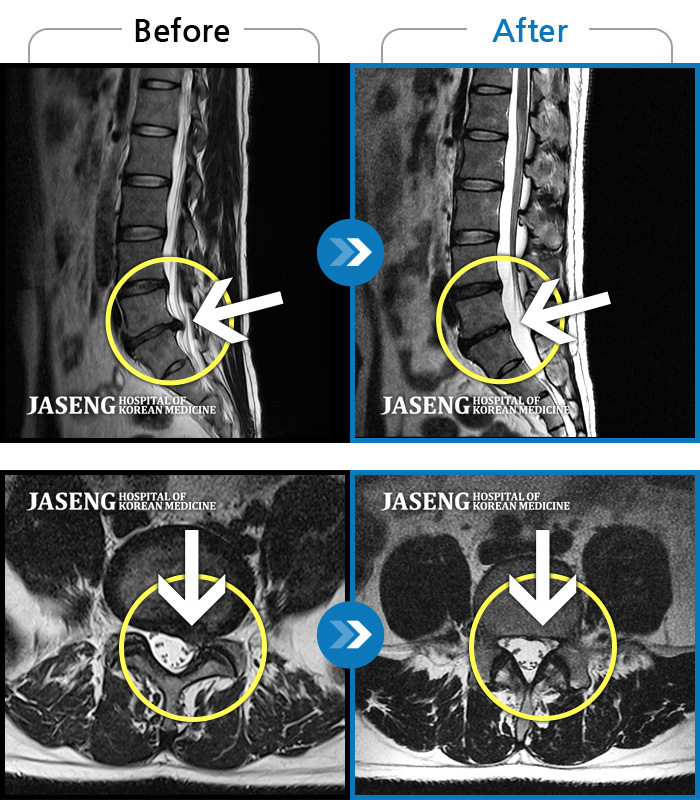

Before

After

환자에게 사전 동의를 받아 동일 조건에서 촬영되었습니다.

개인에 따라 치료 후 부작용이 발생할 수 있으니 의료진과 상담 후 치료를 진행하시기 바랍니다.

우측 허리부터 골반 통증, 우측 다리까지 이어지는 저림감, 10분이상 앉아있기 어려움

처음 내원 시 우측 엉덩이가 많이 아프고, 우측 다리로 근력 및 감각 저하도 있어 발목 움직임이 원활치 못했으며, 야간통으로 잠도 못 자고 통증 심하여 정상적인 활동이 힘든 상태셨습니다.